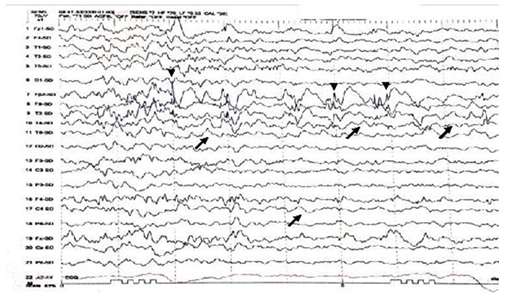

A twelve years old right handed boy a school student referred to the epilepsy monitoring unit for epilepsy surgery evaluation of pharmaco-resistant epilepsy that failed several antiepileptic drugs monotherapy and poly therapy trials. The patient is a product of full term normal spontaneous vaginal delivery with normal mile stones. He had febrile convulsions at the age of one year with no recurrence and had family history of epilepsy with one sibling and one paternal cousin had epilepsy with generalized tonic clonic seizures in remission on anti epileptic drugs. The first generalized tonic clonic seizure occurred at the age of seven years preceded by an aura of rising abdominal pain and followed by post ictal fatigue. Generalized tonic clonic seizures recurred at weekly interval with and without the preceding abdominal pain. At times the abdominal pain occurs with no generalized tonic clonic seizures but followed by lack of concentration and fatigue. The seizures occurred mainly during wakefulness but could occur during sleep. The patient never achieved seizure remission and never developed status epilepticus despite frequent seizures. He was admitted to the epilepsy monitoring unit EMU at the age of twelve years. He was on two antiepileptic drugs namely topiramate one hundred milligram twice daily and lamotrigine two hundred milligram twice daily with almost weekly seizures. His neurological, general and systemic examinations were normal. The patient was kept on his antiepileptic drugs and had five days video electroencephalography EEG monitoring using ten-twenty system scalp EEG electrodes with additional anterior temporal electrodes T1 electrode on the left anterior temporal region and T2 electrode on the right anterior temporal region respectively. During the video EEG monitoring the patient developed four stereotyped electroclinical seizures. Three were during wakefulness and one during sleep. No generalized tonic clonic seizures recorded. The seizures were preceded by abdominal pain in one seizure only. The seizure semiology starts with abrupt asymmetric abduction of both upper and lower limbs with prominent tonic and dystonic contraction of the left upper and lower limbs and adversive eyes and head deviation to the left with proximal automatic movements of the right arm and leg. The duration of seizure was fifty to sixty seconds during which the patient was unresponsive with early recovery of comprehension and speech in the post ictal phase. The ictal EEG onset starts with right frontal regional suppression followed by slow activity of the right hemisphere in all recorded seizures. The interictal EEG showed asymmetric background with excessive slow transients of three to five hertz activity in the right hemisphere with frequent repetitive interictal spikes and polyspike-wave discharges at right frontopolar region intermixed with two to three slow transients (Figure 1). The electroclinical seizures recorded favored right hemispheric epilepsy with early engagement of the right frontal regions. Preadmission MRI of the brain showed right hippocampal sclerosis HS. Ictal single-photon emission computed tomography SPECT with technetium-99m hexamethyl-propylene amine oxime Tc-99m HMPAO injected at twenty five seconds after ictal EEG onset of the fourth seizure showed right medial and lateral temporal lobe hyperpefusion (Figure 2). Interictal positron emission tomography with F-18 fluorodeoxyglucose F-18 FDG-PET showed right hemisphere hypometabolism with marked reduction of F-18-FDG metabolism at right frontal, right temporal, right parietal and right thalamic regions (Figure 3). As the initial MRI diagnosis of right HS could not alone explain the seizures of the patient with a high probability of additional right hemispheric neocortical focus a follow up high resolution three Tesla MRI brain was performed prior to invasive EEG recording. The MRI brain clearly demonstrated right temporal pole cortical dysplasia in addition to the right HS (Figure 4).The diagnosis of dual pathology was made with right temporal pole cortical dysplasia and right HS the so called HS+. The patient underwent directly epilepsy surgery without invasive EEG implantation .He received extensive right temporal lobectomy under intraoperative electrocorticography and regions with active spiking were removed (Figure 5). Histopathology of the resected right hippocampus showed HS and tissue from the right temporal pole confirmed the presence of focal cortical dysplasia type III. The patient had no post surgical complications. The patient became seizure free and six month post epilepsy surgery interictal EEG was normal. Currently the patient is seizure free with significant cognitive improvement at five years post epilepsy surgery on lamotrigine 25mg once daily .He attends high school and plans to be a teacher.

Figure 1 Interictal EEG shows asymmetry of EEG background with excessive slow transients of 2 to 3Hertz Hz in the right hemisphere (black arrows). Intermixed spikes and poly spikes wave discharges at the right fronto-polar regions FP2 (arrow heads).